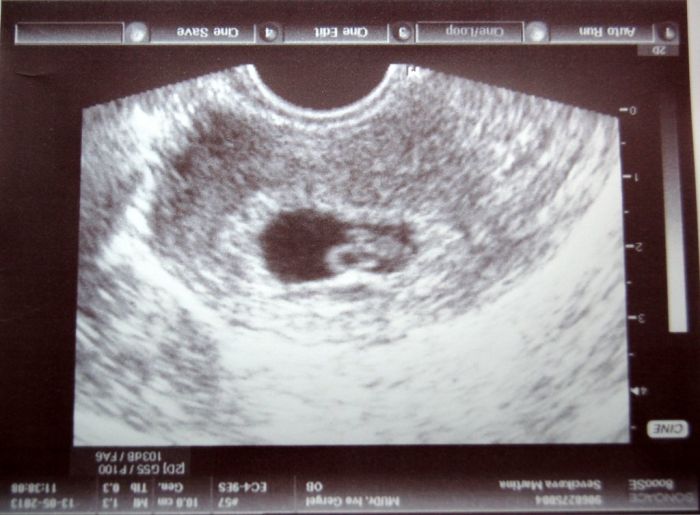

Holky, tak mám konečně fotečku a pochlubím se Vám :) Doktorovi se akorát nelíbila moje pánev a moc jsem to nepochopila a do průkazku mi napsal k položce pánev: 32, 31, 33/19! moc jsem nepochopila ten vykřičník. Termín mi posunul ze Štědrého dne na Silvestra :)